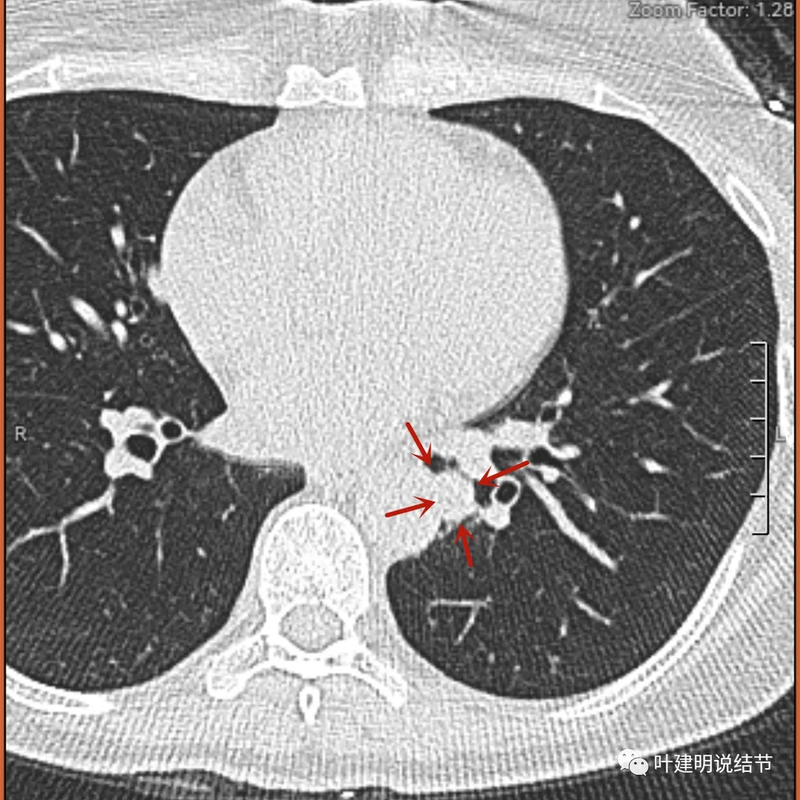

再看2024年5月时复查的影像:

分叶,混合偏实性密度,血管贴边走行。

与支气管紧贴,黄色箭头所示处似乎支气管壁与病灶已经愈着。

上图又见结节与支气管不是都愈着的,说明侵袭性并不强,病灶表面光滑。

天蓝色箭头所指处是北段支气管与病灶之间,感觉较2月份贴得近了一点点。病灶表面仍是光滑的,总体感觉有膨胀性。

病灶边缘光滑,有血管穿出来似的。

表面光滑,有膨胀性。

内部密度较为均匀,就位于肺门部。

边缘光滑,实性,有膨胀感。

与血管关系近。

边缘区域与下肺静脉间隙不太清楚。